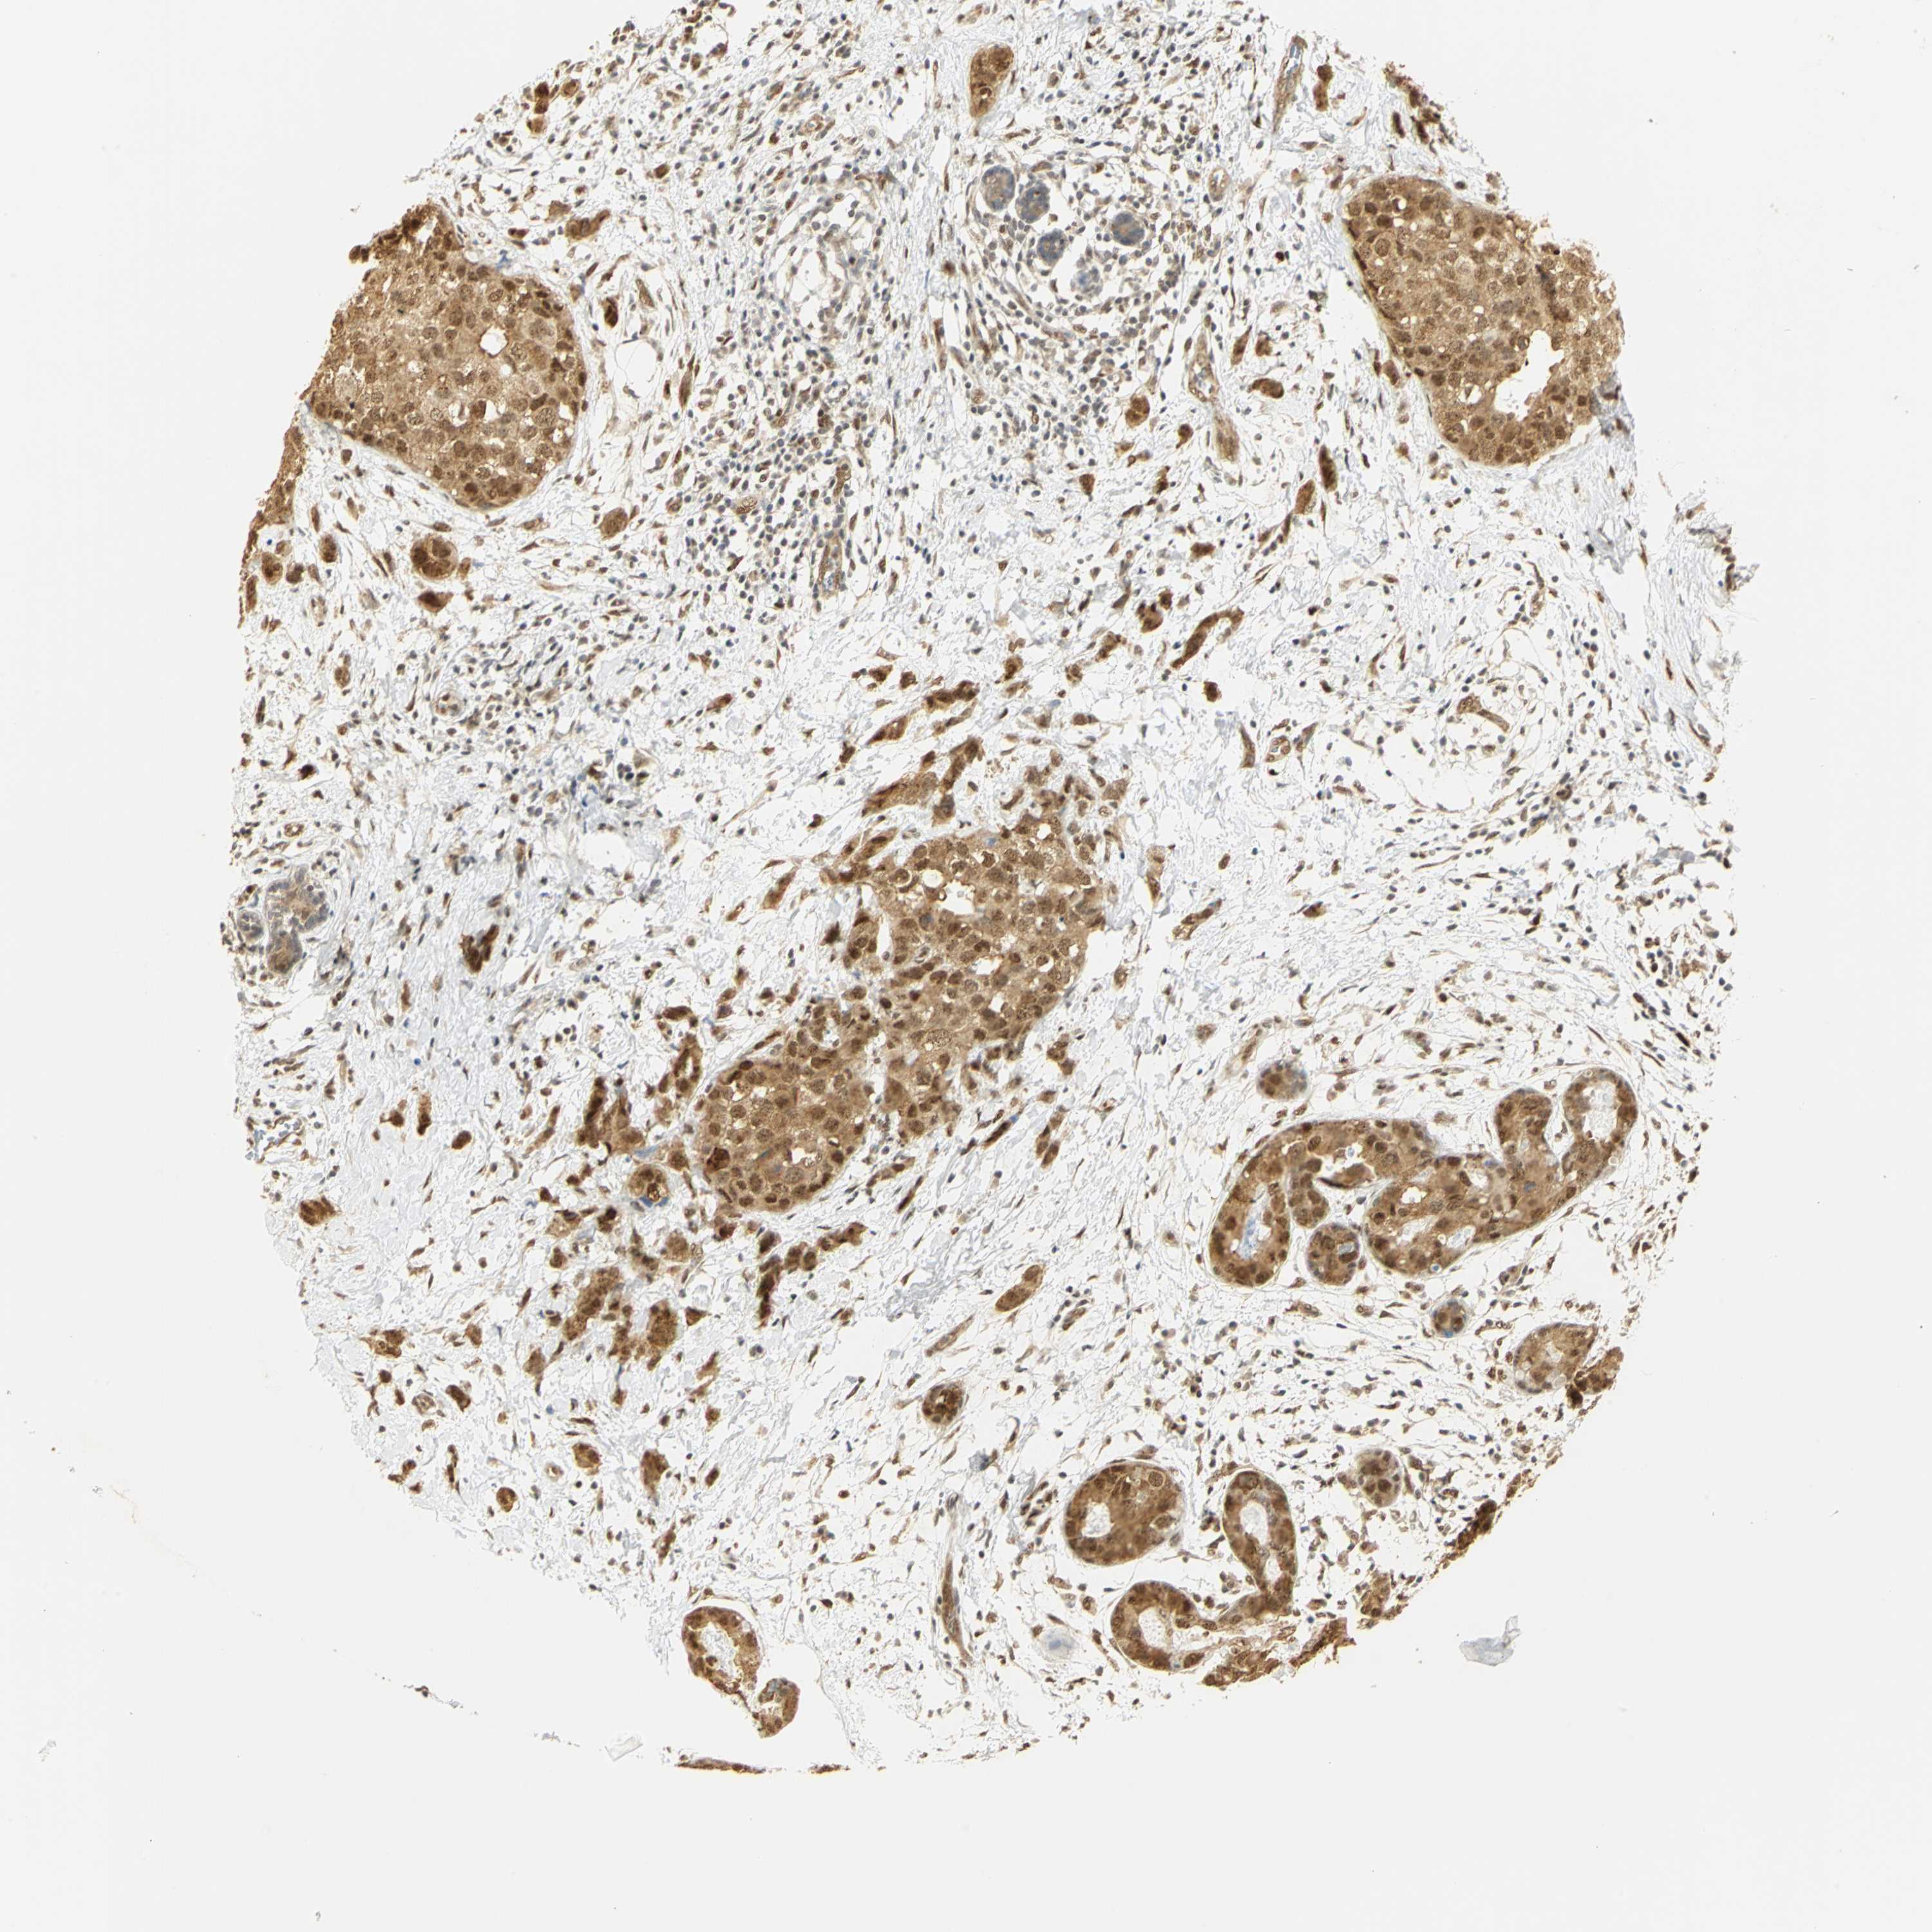

BRCA TCGA BRCA VALIDATION PROTEIN EXPRESSION